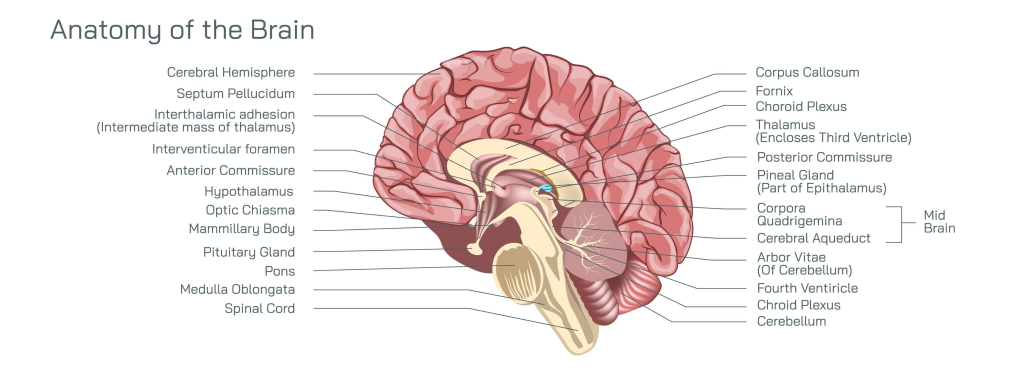

Beyin Anatomisi ve Temel İşlev Haritası

Cerebral Hemisfer (Beyin Yarımküresi)

Septum Pellucidum (Şeffaf Bölme)

İnterthalamik Yapışıklık

İnterventriküler Delik (Monro)

Anterior Commissure (Ön Bağlantı)

Hipotalamus Optik Kiazma

Mammiller Cisim

Pitüiter Bez (Hipofiz)

Pons (Köprü)

Medulla Oblongata (Omurilik Soğanı)

Spinal Kord (Omurilik) Corpus Callosum (Nasır Cisim)

Fornix (Kemer)

Koroid Pleksus

Talamus

Posterior Commissure (Arka Bağlantı)

Pineal Bez (Epifiz)

Corpora Quadrigemina (Dörtüz Cisim)

Serebral Akuedukt (Sylvius)

Arbor Vitae (Hayat Ağacı)

Dördüncü Ventrikül (Karıncık)

Koroid Pleksus

Serebellum (Beyincik)

• Nefs-i Emmare (Dürtüsellik), şemada Pons ve Medulla’nın hemen üzerinde bulunan Amigdala (Limbik Sistem) ile ilişkilidir.

• Nefs-i Mutmainne (İrade ve Huzur), şemanın en önünde (Cerebral Hemisfer’in ön ucu) bulunan Prefrontal Korteks ile ilişkilidir.

• Nefs-i Safiye (Fena Hali), Cerebral Hemisfer’in arka-üst kısmındaki Pariyetal Lob aktivitesinin azalmasıyla gerçekleşir.